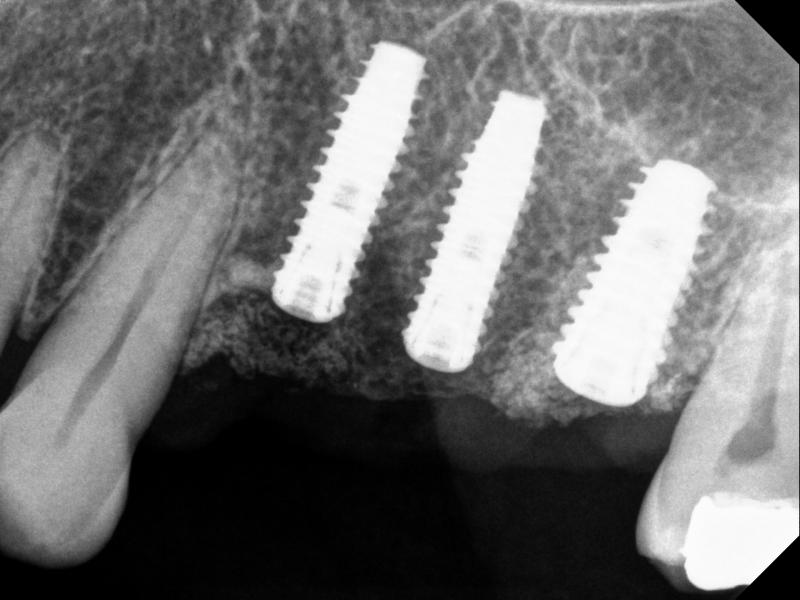

Multiple Implants

The following is an example of a multi-implant case, in which there is no room for error. Thus, a fully-guided system must be used for implant placement (Figs.7 & 8)

Fig. 7. A multi-implant case, fully guided (Sites #12, #13, and #14): planning

(a)

(b)

Fig. 8. A multi-implant case, using fully guided sytem, Sites #12, #13, and #14 -- implants and cover screws: (a) PA, and (b) BW

Note that for Site #14, the implant was tilted a bit to the mesial side (compared to the planning).